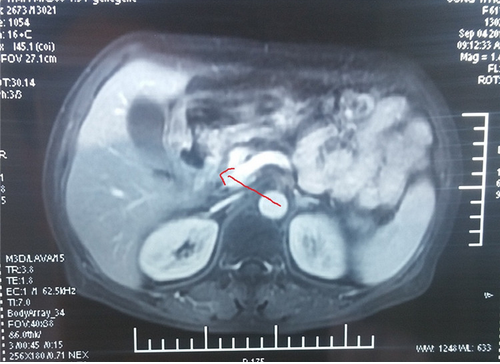

2017-09-03(治疗后)腹部MRI提示:腹腔内无淋巴结肿大。

患者2月前来的我院肿瘤科,考虑到患者年龄大,饮食少,伴有腹痛,体质差,预计生存期3月。我院肿瘤科杨金山副主任医师与中医专家田思强科主任进行中西医结合讨论,充分论证,对这种病情复杂的肿瘤晚期患者,决定采取单药口服化疗及中药调理。单药口服化疗具有副作用小的特点,结合中药扶正祛邪,调节免疫等干预。经2周期的精心治疗,2017-09-03查腹部MRI提示:腹腔内转移瘤消失,胃窦部肿瘤明显缩小。患者饮食、体力状况明显改善,腹痛缓解,能独立正常生活,患者及家属满意。中西医结合治疗凸显了在肿瘤治疗的优势。